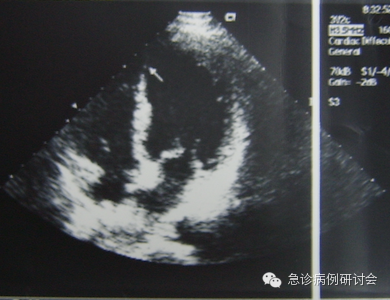

8:30am查超声心动图检查也提示存在节段性室壁运动异常(室间隔中下段及左室心尖部)(见图3)。

图3 时间8:30am